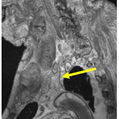

Run a higher resolution localizer, based on the HASTE sequence. Use the multi-station approach to ensure sufficient coverage from the top of the head to the pubic symphysis. Overlap each station by 15% to facilitate stitching of images from different stations into a single DICOM image with full coverage.

Run the Dixon-VIBE scan as defined in Table 1. Ensure inclusion of acromia for landmarking purposes.

Table 1. MRI scan parameters.

Run the CISS scan as defined in Table 1.

Run the VIBE scan as defined in Table 1. Ensure the number of stations and fields of view are exactly matched to CISS scan.

Reformat all data (multiplanar reconstruction, MPR) to convert the sagittally acquired images into axial images.